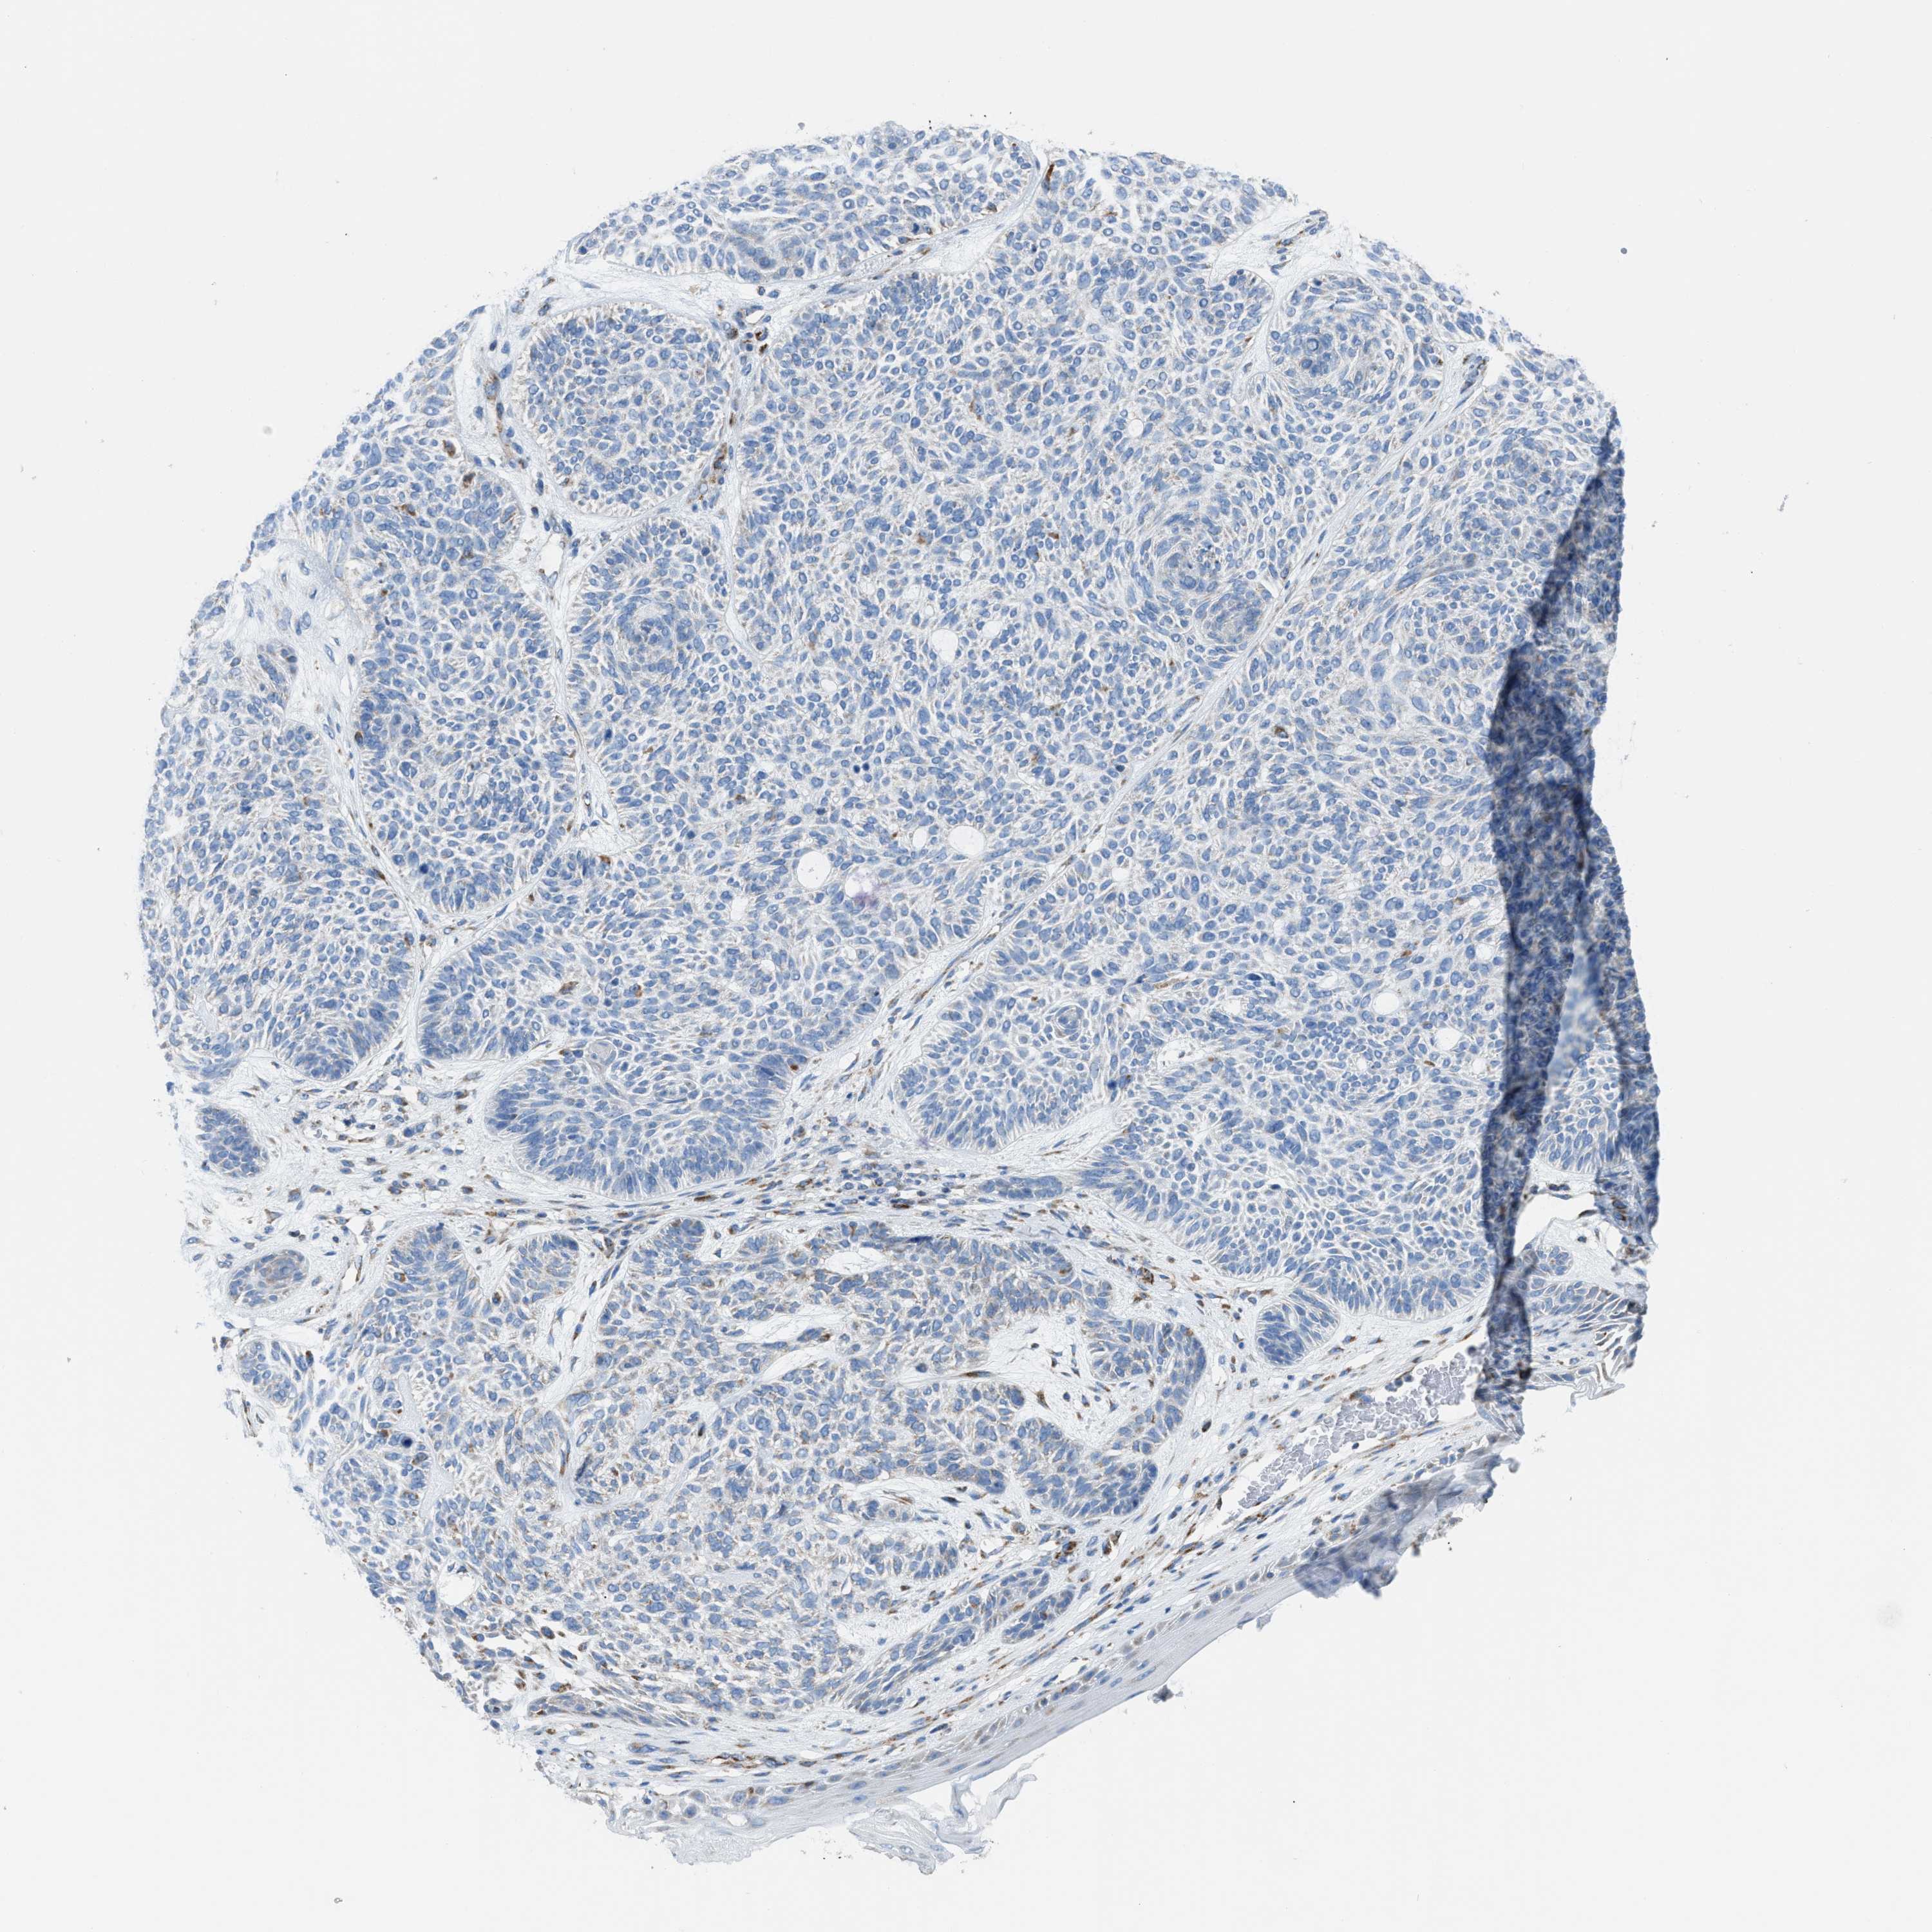

SKIN CANCER - Protein expressioni

A mouse-over function shows sample information and annotation data. Click on an image to view it in a full screen mode. Samples can be filtered based on level of antibody staining by selecting one or several of the following categories: high, medium, low and not detected. The assay and annotation is described here.

Each image is clickable and will lead to virtual microscopy that enables deeper exploration of all samples and also displays staining intensity scores, fraction scores and subcellular localization as well as patient and tissue information for each sample.

Antibody HPA018910

Basal cell carcinoma